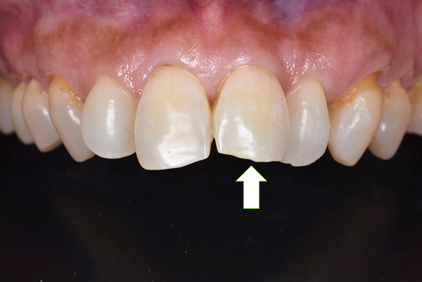

初診時

患者様の主訴は、「前歯の隙間が気になる」

でした。

矯正治療をおすすめしましたが、矯正治療の期間が長いということでセラミック治療を選択することになりました。写真をみるとすきっ歯も気になりますが、以前に詰めたプラスティックも変色して着色しており気になります。

仮歯

セラミックの前に仮歯を調整している段階になります。できればということで歯の長さも短くしたいというリクエストがありましたので、仮歯で調整をしながら様子を見ました。

歯の長さを短くする際に歯を削りますので神経の治療が必要になることがありますので、しみたり・噛んで痛くないか?を約1ヶ月様子を見ました。色・形など仮歯でほぼ問題ないということでしたので、最終的な型採りをしました。

セラミックセット

最終的なジルコニアボンドクラウンをセットしました。すきっ歯がまずなくなりました。また、長かった歯が短くなりましたので本人の希望に沿うことができました。